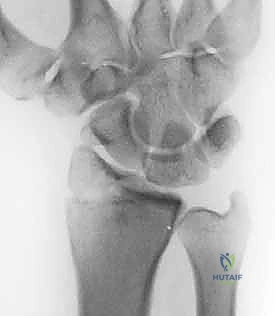

IMAGING AND OTHER DIAGNOSTIC STUDIES

Plain radiographs

Anteroposterior view

Axillary lateral or West Point axillary view Outlet view

Stryker notch view

Evaluate for

Hill-Sachs or reverse Hill-Sachs lesion Glenoid pathology

Bony humeral avulsion of the glenohumeral ligaments (HAGL)